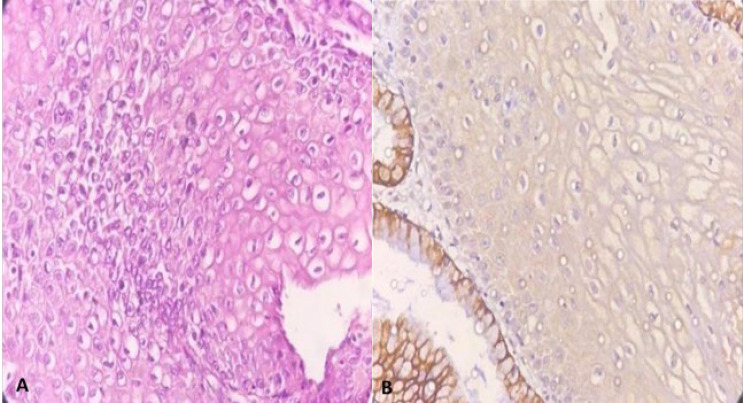

Methods: This retrospective study was conducted in Yas Complex Hospital from 2016 to 2018 among patients of the clinic of colonoscopy. Patients with low-grade lesions were included in one group, and patients with high-grade lesions were considered as a control group. The immunoreactivity of CK7 by immunohistochemical staining pattern was interpreted in both groups.

Results: CK7 immunoreactivity was negative in 29.5% of the precancerous lesions and positive in 70.5%. The relationship between grade and CK7 staining was significant (P = 0.040). A significant relationship between the progression status of the disease and CK7 staining was obtained (P=0.001). CK7 staining showed a sensitivity of 82.35%, specificity of 81.82%, positive predictive value of 87.5%, negative predictive value of 75%, and diagnostic accuracy of 82.14% in predicting the progression of the SILs.